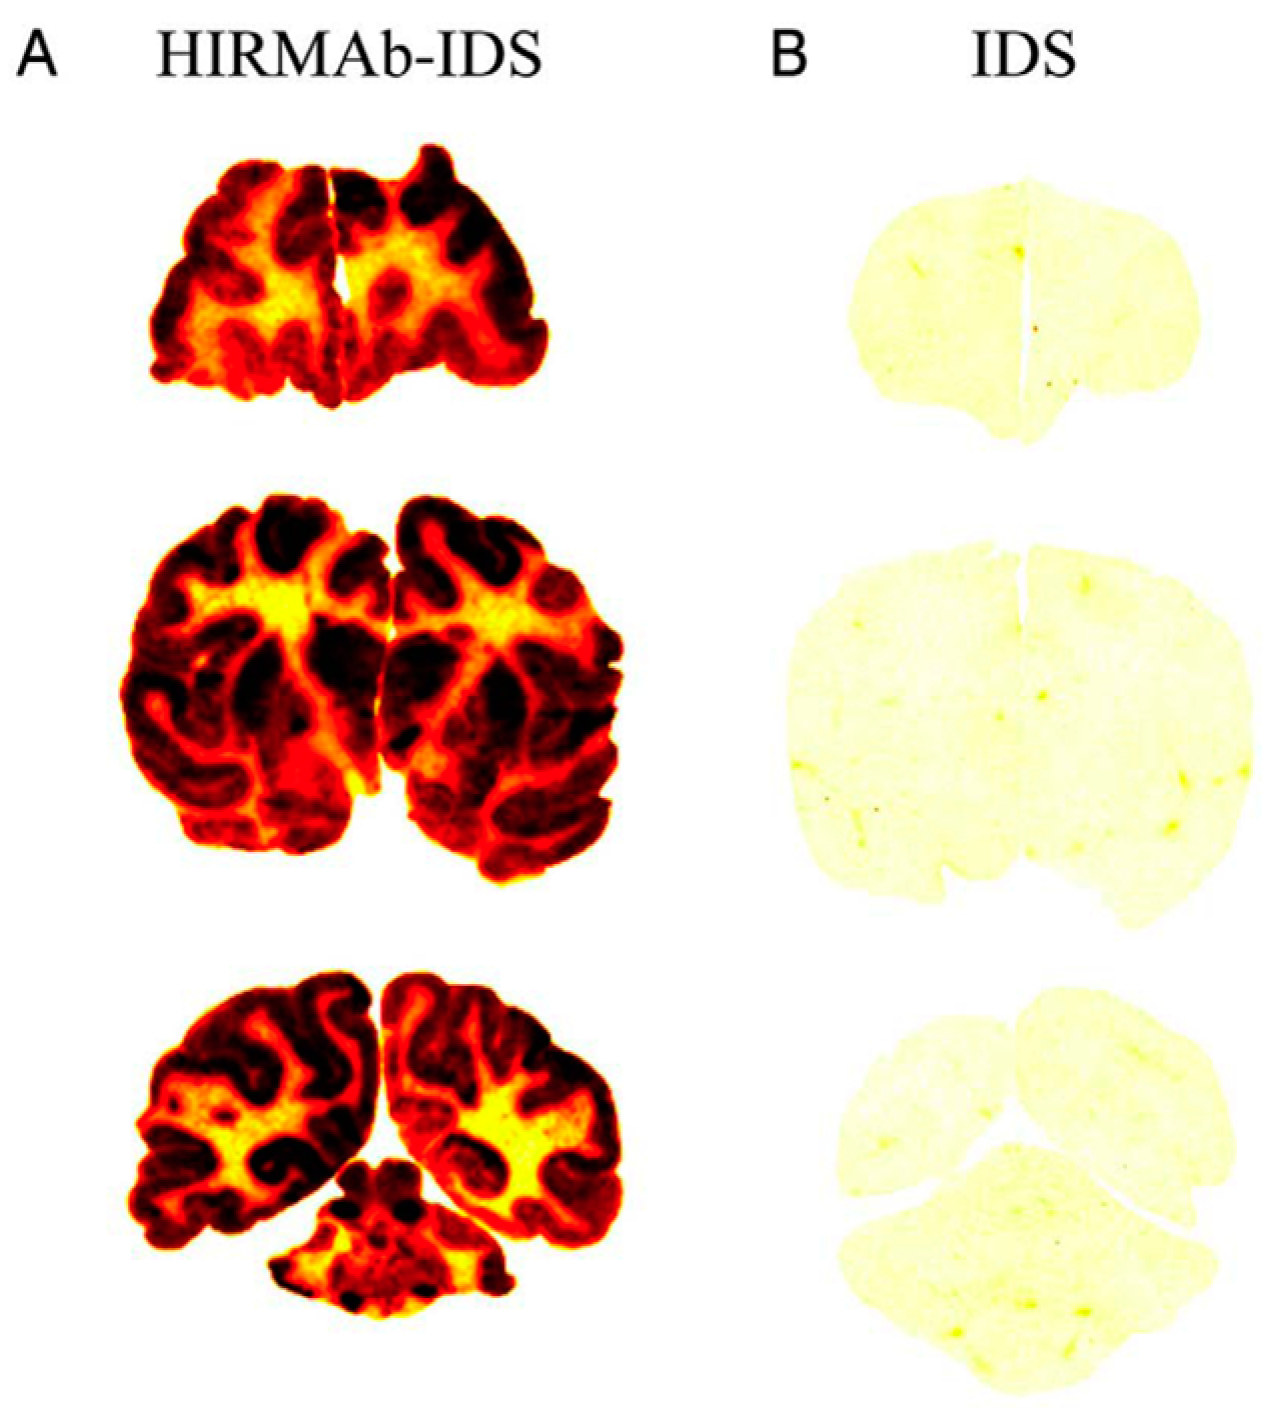

- Lu, J.Z.; Boado, R.J.; Hui, E.K.; Zhou, Q.H.; Pardridge, W.M. Expression in CHO cells and pharmacokinetics and brain uptake in the Rhesus monkey of an IgG-iduronate-2-sulfatase fusion protein. Biotechnol. Bioeng. 2011, 108, 1954–1964. [Google Scholar] [CrossRef] [PubMed]

- Boado, R.J.; Hui, E.K.-W.; Lu, J.Z.; Sumbria, R.K.; Pardridge, W.M. Blood-Brain Barrier Molecular Trojan Horse Enables Imaging of Brain Uptake of Radioiodinated Recombinant Protein in the Rhesus Monkey. Bioconjug. Chem. 2013, 24, 1741–1749. [Google Scholar] [CrossRef]